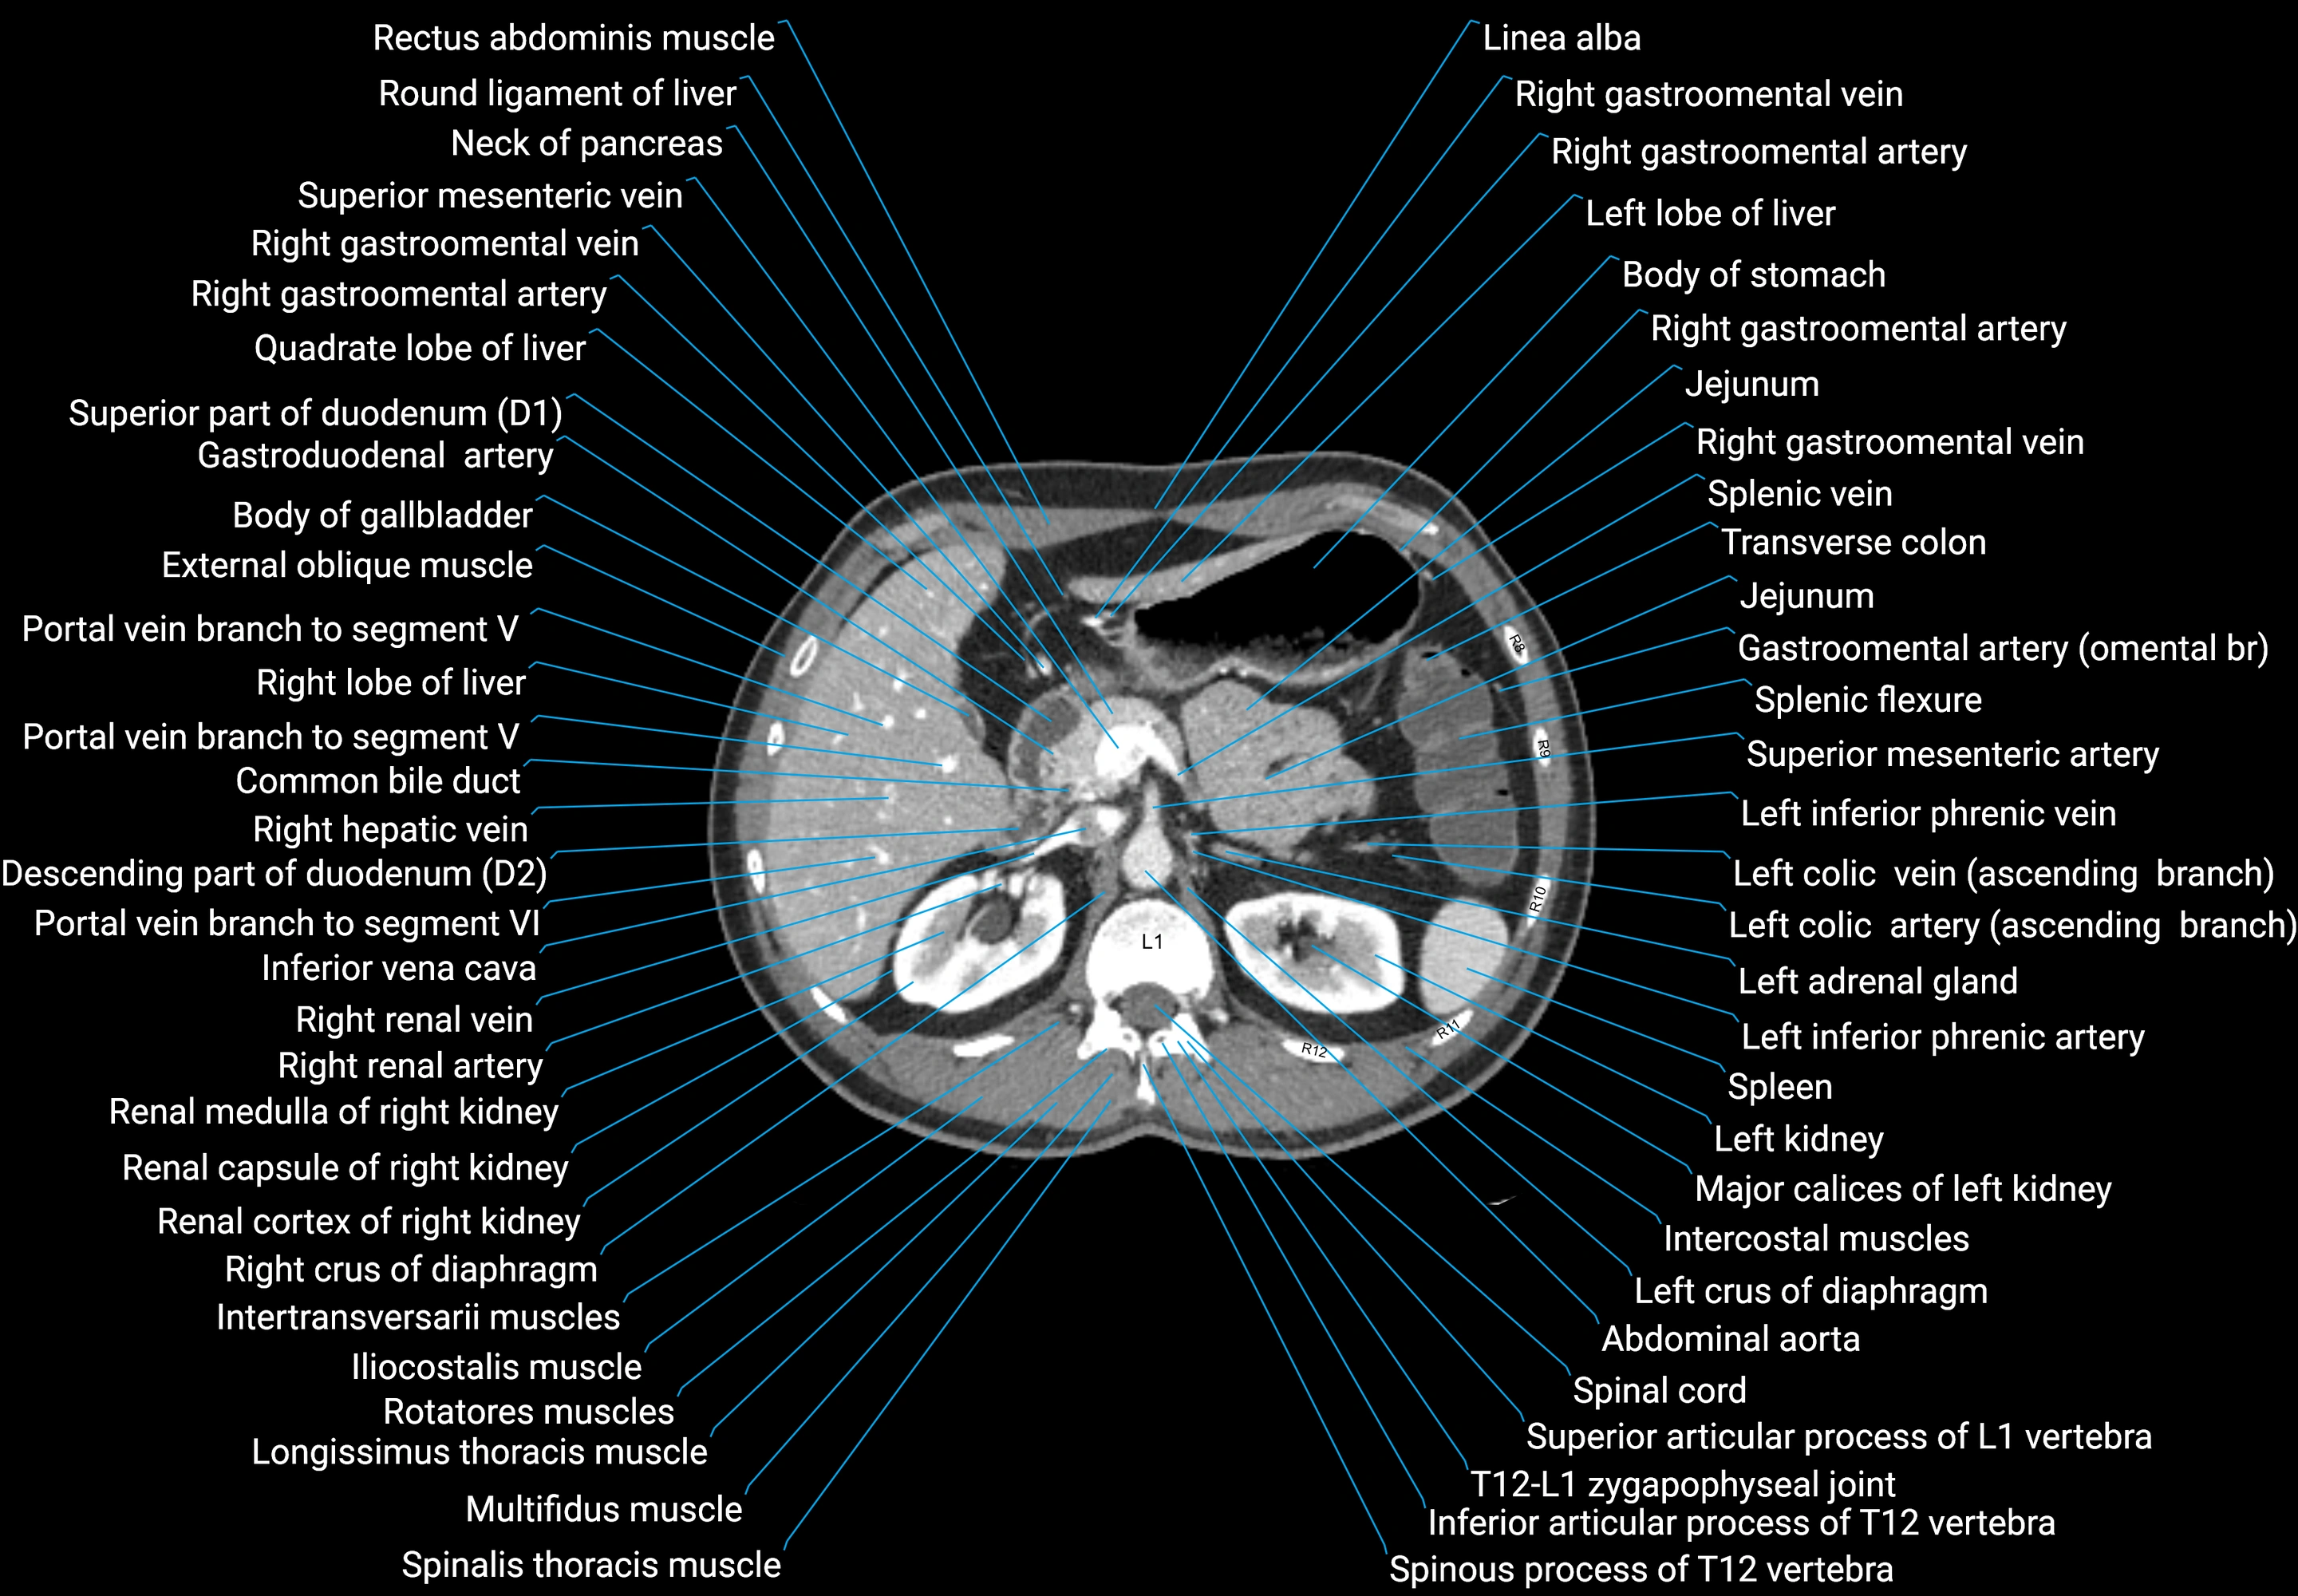

CT images